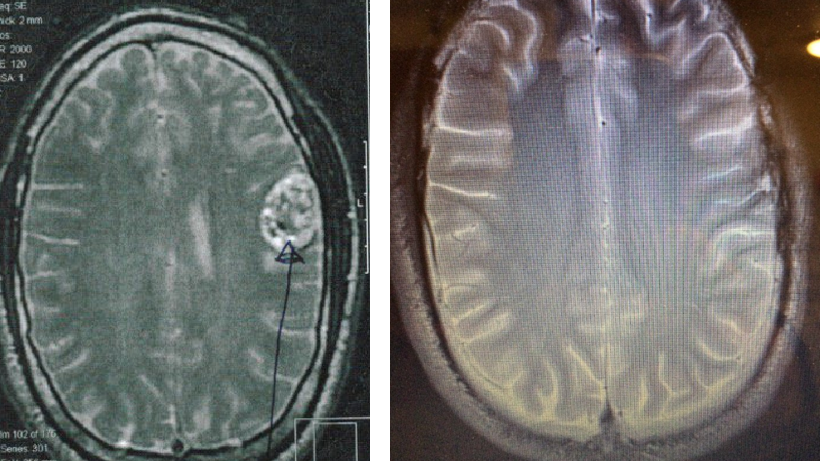

Two and a half years ago 27 year old Andrew Scarborough was suffering from fatigue, headaches and seizures. He suddenly collapsed with the worst headache in his life and was